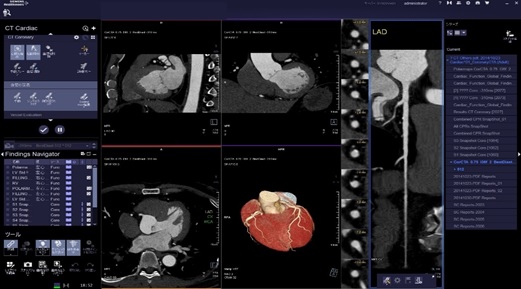

通常検査に加えて心臓CT検査(循環器内科)や大腸CT検査(消化器内科)などの特殊な検査にも対応しています。

当院の装置は管球1回転最速0.28秒と非常に早く、幅広い心拍の方に対応しています。

解析処理は専門のワークステーションを使用し、読影は循環器内科医師と画像診断専門医(遠隔画像診断支援)双方で行い、結果を循環器内科医師よりお伝えしています。